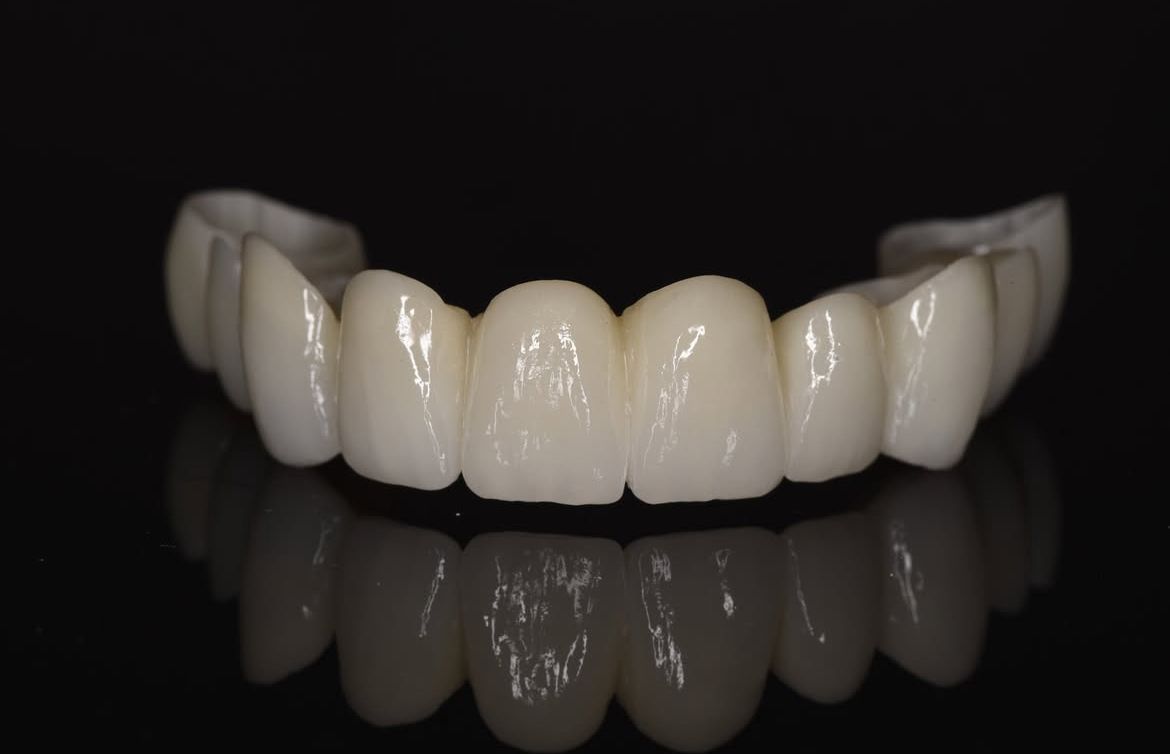

- protetyka (korony ceramiczne (cerkon, E-max), licówki, mosty, protezy ruchome, korony na teleskopach, inlay, onlay, overlay, endkorony);